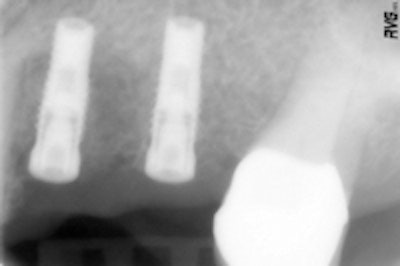

Figure 3 (top): An overview of the system's components, including the manual wrench.Figure 4 (bottom): Radiograph to control the proper position of the Spread-Condense screws.

The Spread-Condense screws can be screwed in with intuition using the hand wrench (figure 3). The laser-etched depth markings are clearly visible during clinical use. Achieved by mechanical clamping, the screw's secure fit allowed for the radiographs to determine the position and the depth without inadvertent aspiration (figure 4).